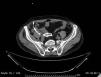

Common and applicable diagnostic methods are available for brucellosis. However, its life-threatening complications remain critical. Herein we present a 68-year-old patient who complained of leg pain for two months. At admission he had absent pulse in the left femoral and bilateral popliteal arteries. Laboratory test results were leucocytes 8700/mm3, CRP 86mg/L, and ESR 47mm/h. Abdominal CT revealed images consistent with mural thrombus in the suprarenal segment of abdominal aorta, total occlusion and hypodense thrombus material completely filling the aortic lumen through infrarenal segment extending to lumens of the caudal, bilateral common and superior iliac arteries (Figs. 1–3). No paleness, coldness or color change was detected in the lower extremities. The patient had fever, right inguinal swelling, and sweating. Abdominal CT showed an aortic thrombus and a hypodense lesion of 58mm×61mm×100mm in the right psoas muscle. The repeated Brucella STA test was positive in 1:5120 titer. USG-guided drainage of the psoas abscess was performed and a treatment with doxycycline and rifampicin was administered for three months (Fig. 4). The patient was not operated on and progressed with no clinical complaints.